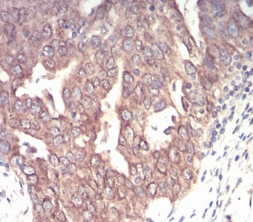

EMD Mouse Monoclonal antibody[8F5A8]

Emerin is a serine-rich nuclear membrane protein and a member of the nuclear lamina-associated protein family. It mediates membrane anchorage to the cytoskeleton. Dreifuss-Emery muscular dystrophy is an X-linked inherited degenerative myopathy resulting from mutation in the emerin gene.

Immunogen:    Purified recombinant fragment of human EMD (AA: 1-222) expressed in E. Coli.

IHC    1/200 - 1/1000